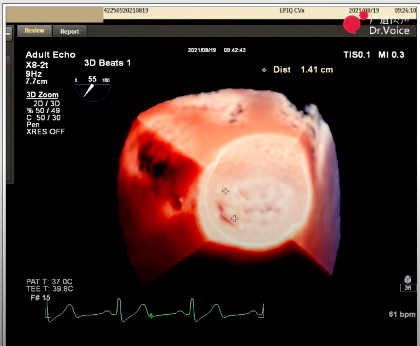

3、经仔细调整输送系统,将瓣夹送入二尖瓣目标位置和预定角度,适当移动瓣夹靠近A1区域,同时兼顾前后瓣叶位置。

瓣夹目标夹闭角度

二尖瓣夹释放后,超声显示反流几近消失,二尖瓣前向峰值流速1.2m/s,平均跨瓣压差3mmHg。患者各项生理指标正常,手术顺利完成,手术操作耗时约120 min。

术后生命体征及超声效果